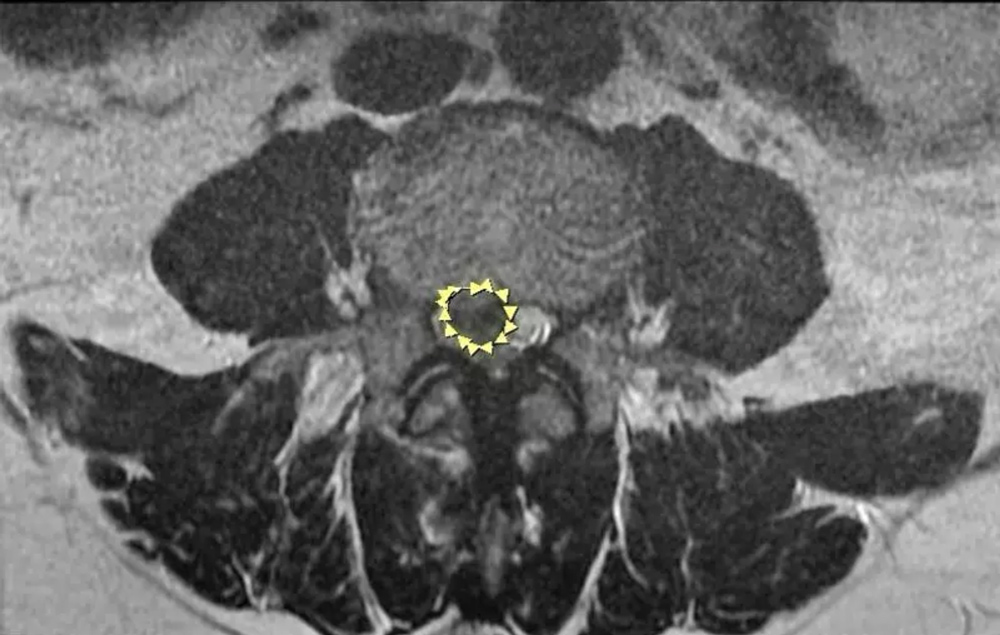

除夕夜,一名49歲女性突發劇烈頭痛、嘔吐,晚間意識不清送醫,檢查發現大量蜘蛛膜下腔出血及腦室內出血,確診為顱內動脈瘤破裂。急診立即插管,並由神經外科完成動脈瘤夾閉手術,大年初二剛好是患者生日,術後逐漸恢復清醒,四肢活動正常。

腦動脈瘤破裂引起的出血(箭頭處)。腦動脈瘤破裂引起的出血(箭頭處)。